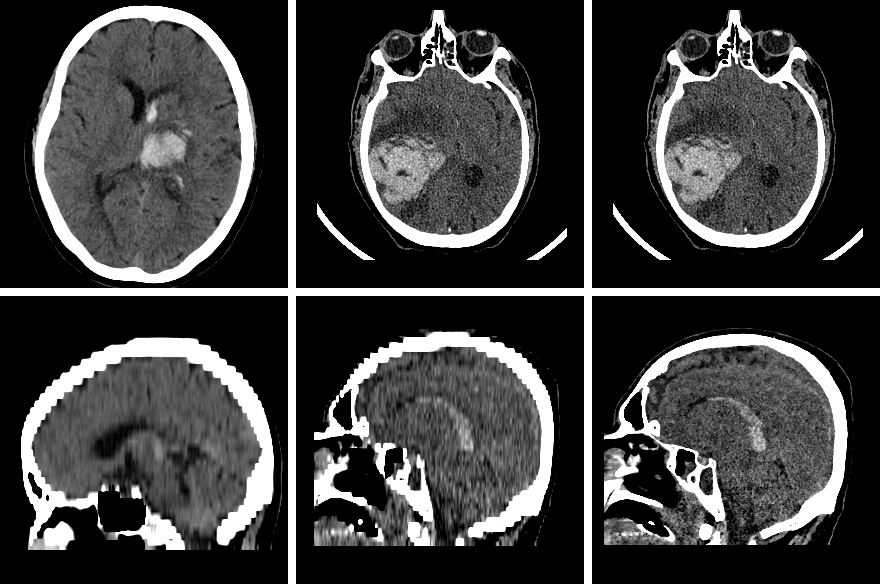

It is constituted of 18 head CTs of patients diagnosed with intracranial hemorrhage between 2021 and 2022. As shown in Fig. 4, this dataset contains out-of-distribution cases, both in terms of bleeding size and number.

These images are high-resolution head CTs and have a native voxel spacing of 0.410.410.3mm3.

As such, we resampled them to a voxel spacing of 0.410.415mm3 for inference (see Fig. 5), to match the resolution of the training data.

This ablation aims to shed light on the drop of performance of our method on the private cohort. In particular, one might recall that the bleeding size distribution is significantly different from the distribution in the training set. As such, we additionally give the performance of our method on each size group (Table 3). We can observe the steepest drop in performance from INSTANCE2022 to the private cohort for both the smallest and largest bleeding. The former can be expected, as smaller bleeding are harder to detect and are more prevalent in the private cohort. However, the latter phenomenon is due to a strong distribution shift of the cerebral scene. Indeed, the private cohort also contains trauma patients with severe hemorrhages but also fractures or even an open skull. No similar cases are present in the training set.